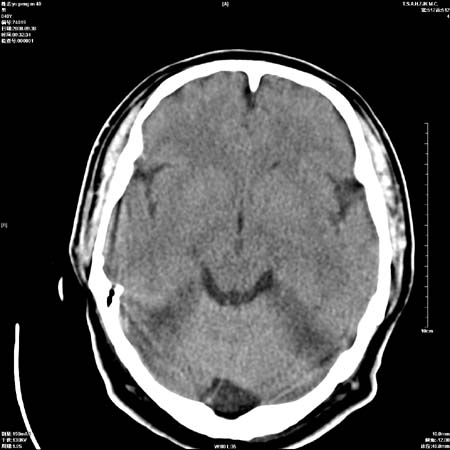

以下是引用流浪星在2008-10-4 20:06:00的发言:[br]大脑大静脉池增宽,脑萎缩引起,目前的ct表现不能解释临床症状,建议短期复查或做mr检查。